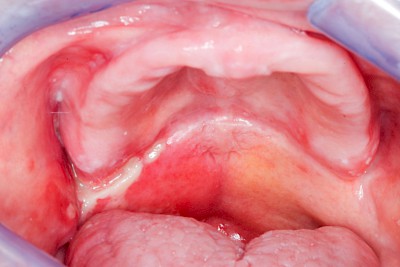

Prothesenstomatitis

Rötung im Bereich der Prothesen-Auflageflächen

Großfläche Rötungen sind häufig auf chronische Entzündungsprozesse bedingt durch die ständige Auflage der Prothese auf der Schleimhaut mitunter 24 Stunden am Tag zurückzuführen (feuchte Kammer). Ganz selten sind spezifische Unverträglichkeistreaktionen wie z. B. Allergien gegen Inhaltsstoffe der Prothesenmaterialien die Ursache. Alle diese Prozesse können unter dem Oberbegriff Prothesenstomatitis zusammengefasst werden.